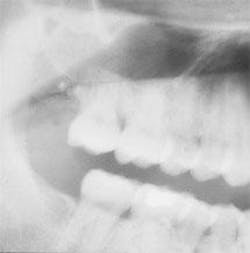

The patient's vital signs were found to be within normal limits. Examination of the head and neck region revealed no enlarged or palpable lymph nodes. Examination of the soft tissues of the oral cavity revealed no unusual findings. Radiographic examination revealed a large radiopacity projecting from the floor of the left maxillary sinus (see radiograph). The radiopacity appeared as a smooth, dome-shaped, homogeneous mass. The teeth adjacent to the left maxillary sinus were tested for vitality; all tested vital.

Radiographically, the antral pseudocyst appears as a dome-shaped radiopacity extending from the floor of the maxillary sinus. The lesion appears as a homogeneous, soft-tissue radiopacity. The borders of the lesion exhibit the same density as the body of the mass and normal anatomic landmarks can be seen through the image of the mucous retention cyst. The antral pseudocyst most often occurs unilaterally, but may also be seen bilaterally.